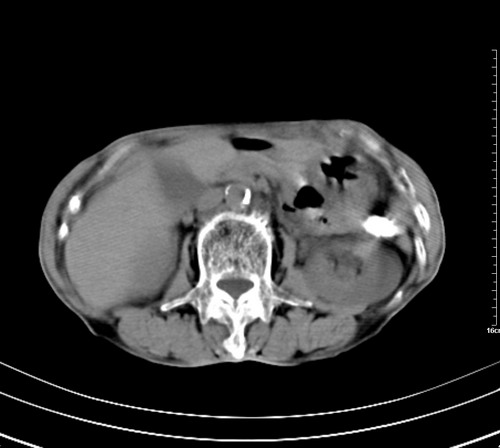

病人,女,79岁,主要因腹疼二月入院,彩超,肝,胆,脾,未见异常,胸透上消化道造影未见异常,化验白细胞增高,内科医生让做胸部ct检查,因为熟人多做了腹部(外科会诊考虑胆囊炎).现ct片如下请假各位战友.

1 气管旁、隆突下淋巴结明显肿大,肝左叶外侧段低密影,都考虑转移。

2 肝右后叶下段明显增大,片状低密影,但因各种伪影显示不佳,不排除病变。

后中纵隔团块影,伴气管、食道受压移位,首先考虑转移瘤,肝s5段低密度灶。建议增强检查,另外其结肠是否有问题请提供,右肺部分肺叶局限含气增多,考虑局限肺气肿。

后中纵隔团块影,伴气管、食道受压移位,首先考虑转移瘤,肝表现同11773。